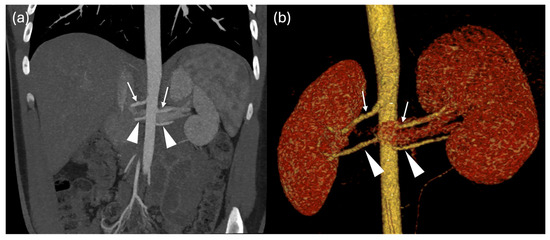

Multiple Renal Arteries as a Potential Contributor to Hypertension in Children and Young Adults

Background: Arterial hypertension in childhood is an increasing health concern, often associated with structural and functional cardiovascular or renal alterations. This study aimed to investigate the prevalence and type of non-stenotic renal artery anatomical variants in children with systemic hypertension and to assess their possible association with cardiac involvement. Methods: A total of 107 children and adolescents with hypertension (mean age 15.4 ± 2.7 years) were evaluated. Hypertension was defined as blood pressure persistently above the 95th percentile for over one year, confirmed by 24 h ambulatory blood pressure monitoring. Patients with known secondary causes were excluded. All underwent renal vascular imaging by CT or MRI and echocardiographic assessment of left ventricular morphology and function. Results: Renal artery anatomical variants were found in 69 of 107 patients (65%), mainly unilateral or bilateral accessory polar arteries. Other anomalies found (left renal vein narrowing or duplication, severe left renal artery stenosis) were excluded from the statistical analysis. Normal renal vasculature was observed in only 32%. Left ventricular hypertrophy was detected in 41%, highlighting a significant prevalence of target-organ involvement. No statistically significant differences were found in terms of hypertension or hypertrophy between patients with renal artery anatomical variants and those without. However, patients with renal anomalies more frequently required dual antihypertensive therapy (p = 0.025). Conclusions: Renal artery anatomical variants, even in the absence of overt stenosis, may contribute to the pathogenesis of pediatric hypertension and complicate its management. Systematic evaluation of renal vasculature should be considered in the diagnostic workup to improve risk stratification and guide management strategies.

Figure 1